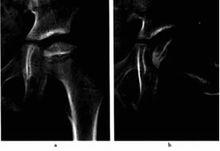

3左側投骨頭骨骺缺血性壞死(進展期)圈9-3左側投骨頭骨骺缺血性壞死(進展期)

a.b平片,示左股骨頭骨骺密度變扁、碎裂,密度不均勻增高,乾骺端稍增寬